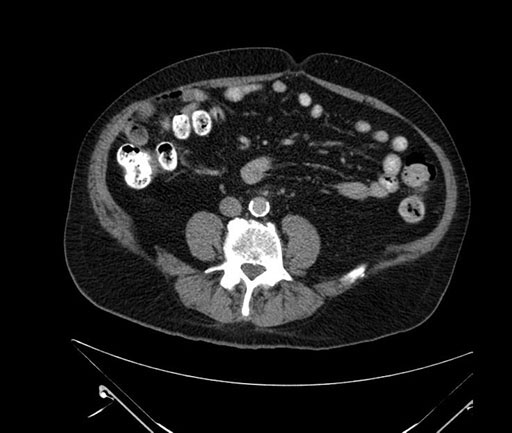

Whipple (pancreaticoduodenectomy) [case 7]

Imaging Analysis

Look through the patient's CT scan to identify any areas of concern for the necessary procedure.

Axial - 3 months prior